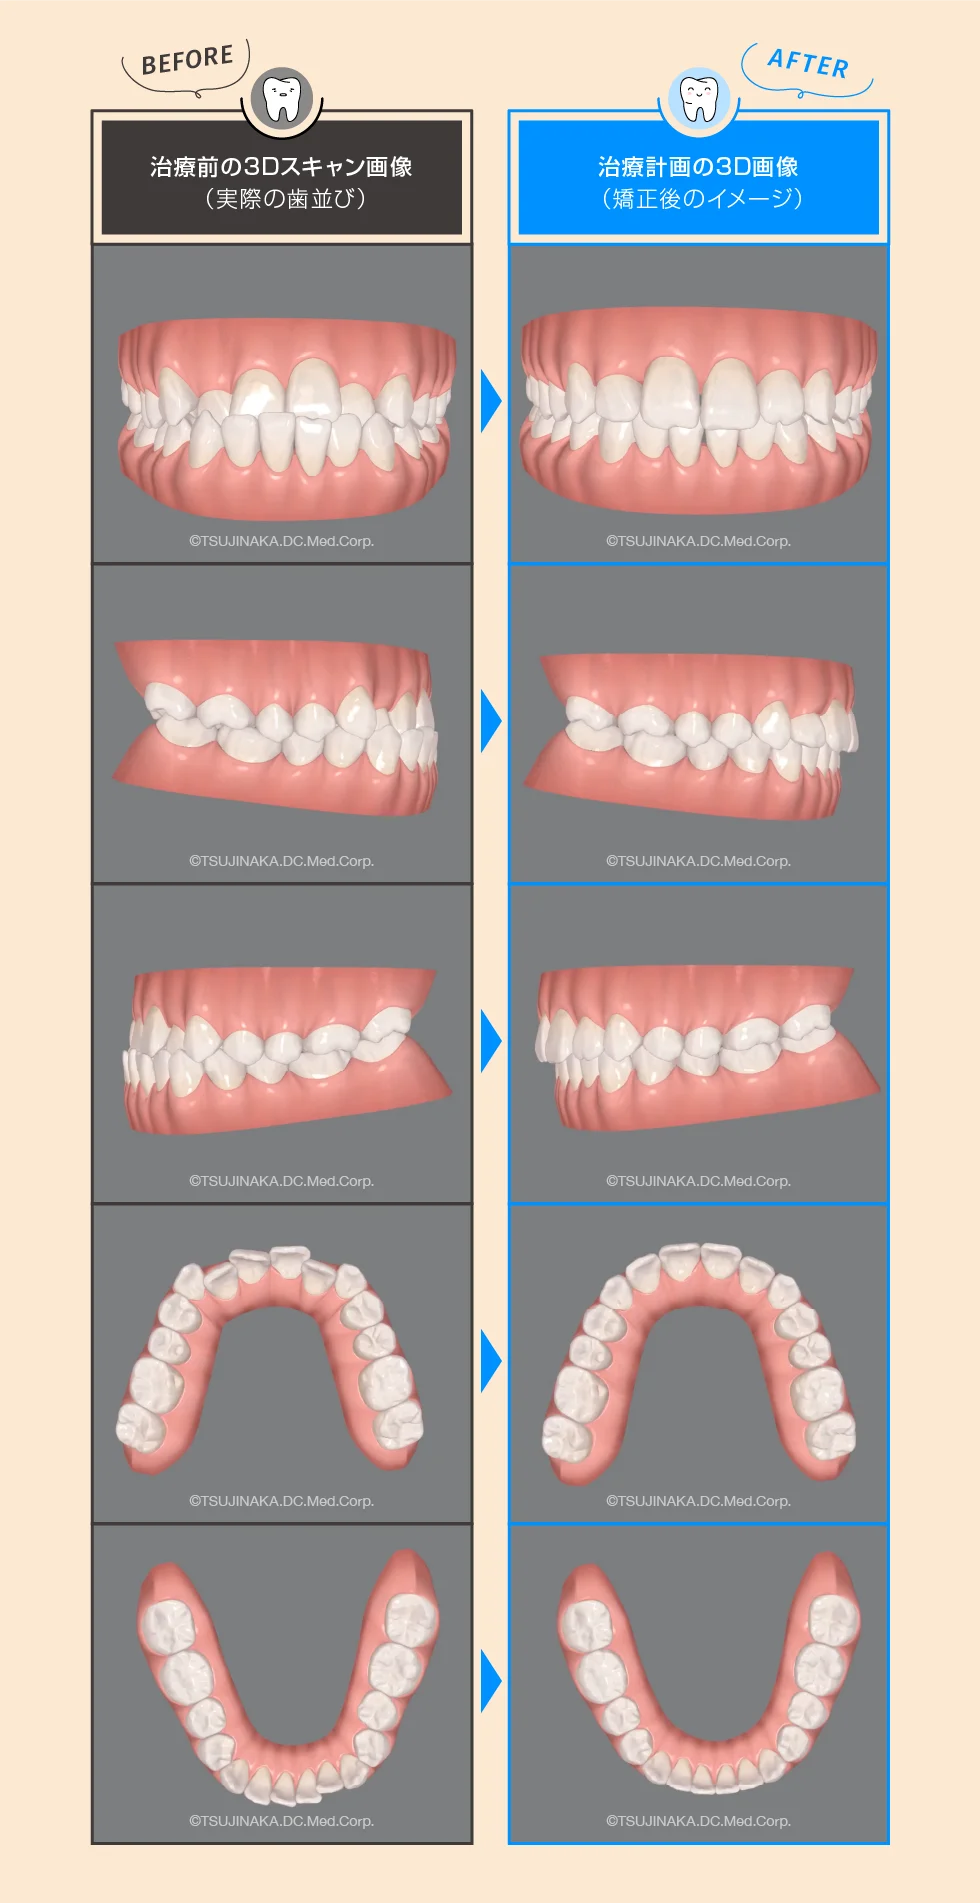

【BEFORE】治療前のiTeroによる3Dスキャン画像です。

【AFTER】iTeroを使って作成した治療計画の3D画像です。

下にある治療前の歯並びを写真撮影したものと見比べてみてください。iTeroでかなり厳密に3Dスキャンできていることがお分かりいただけると思います。